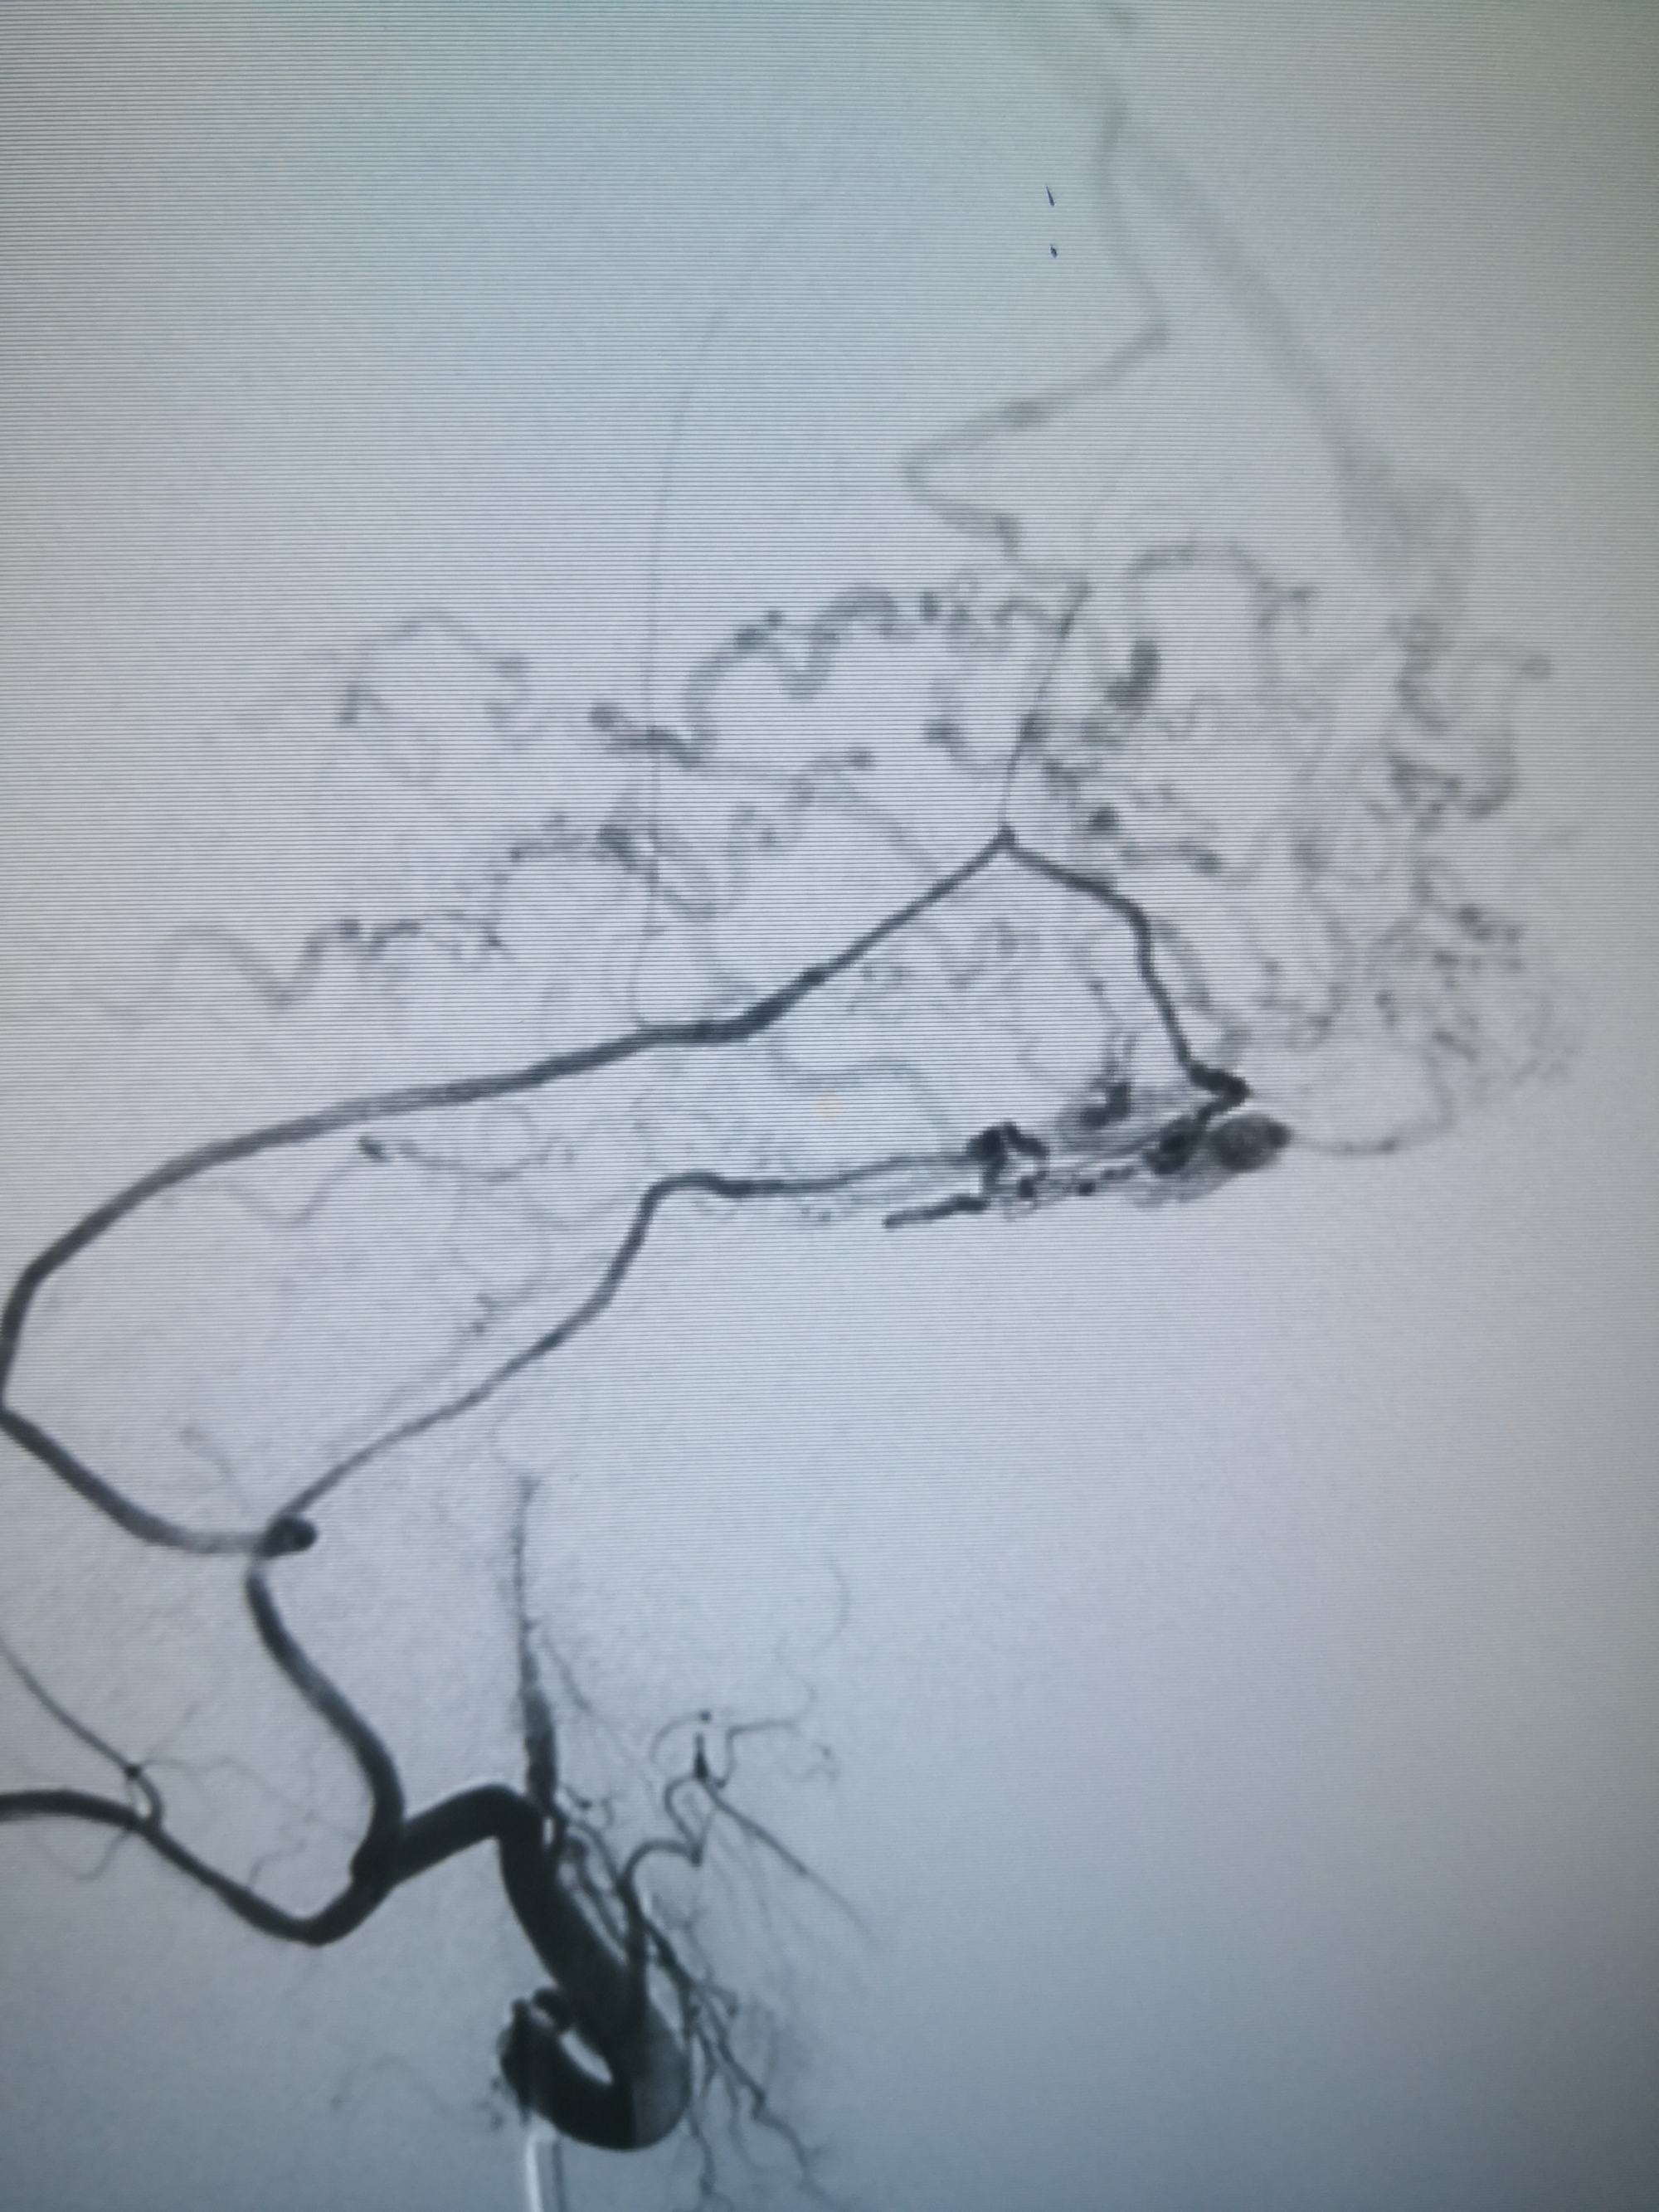

不减影,看看胶

硬脑膜动静脉瘘介入栓塞术后

不减影,看看胶